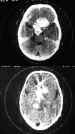

Figura 50. Los tumores hematopoyéticos (leucemias) se presentan en

la órbita como infiltración de una manifestación sistémica.